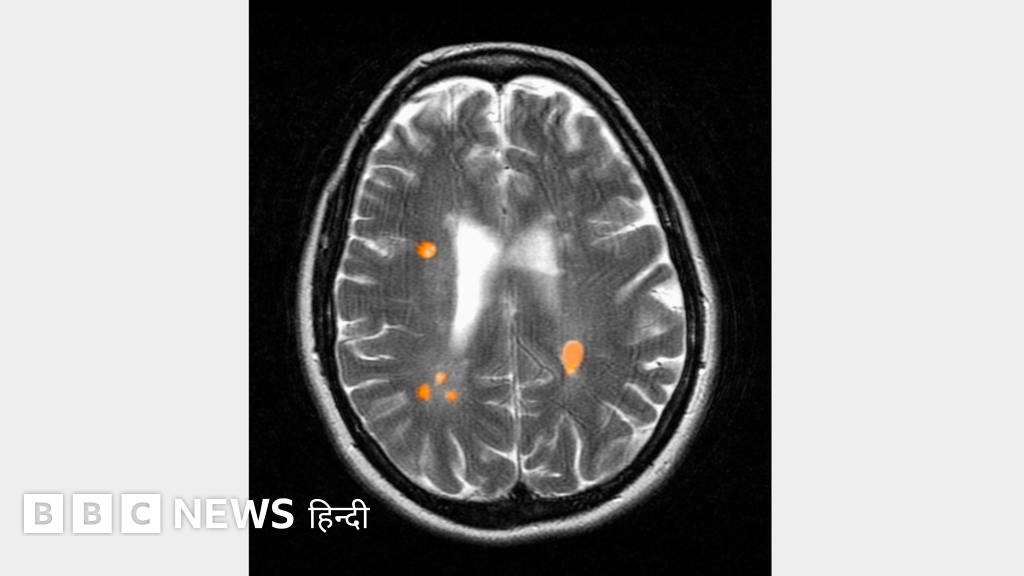

मल्टीपल स्क्लेरोसिस या एमएस एक न्यूरोलॉजिकल बीमारी है. इसके कुछ लक्षणों में थकान होना, हाथ या पैरों में संवेदना कम हो जाना, चलने फिरने में मुश्किल पैदा होना या दृष्टि खो देना शामिल है. आमतौर पर स्कैनिंग के ज़रिए मष्तिष्क या रीढ़ की हड्डी में घाव या किसी प्रकार के नुक़सान को देख कर शरीर में एमएस के संक्रमण का पता लगाया जाता है.